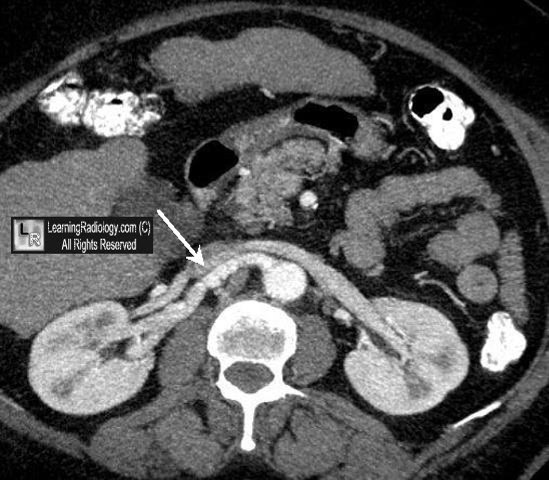

The string of pearls or beads sign can be seen on upright or decubitus abdominal radiographs as well as on ct in patients with small bowel obstruction increased intraluminal fluid and slow resorption of intraluminal gas.

Plain film beaded airway dilatation with or without mucous impaction finger in glove. Signs described on ct include. There are intermittent narrowed and dilated segment to the affected bronchus when viewed in long axis and can give a string of pearls sign 2 reflecting the irregularly beaded appearance. Abpa tends to affect the upper lobes.

Bronchial lumen assumes a beaded string of pearls configuration with sequential dilatation and constriction. Bunch of grapes sign 9. For radiology cases discussion join. Radiology made easy on facebook subscribe to our.